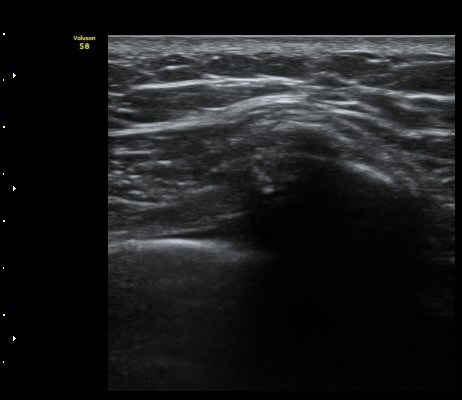

ÃÊÀ½ÆÄ °Ë»ç

¹Ì¼¼ÇÏ°Ô °¥ºñ»À ÇÇÁú°ñ ¿¬°á¼º ¼Ò½Ç°ú ¿¬ºÎÁ¶Á÷ ºÎÁ¾ÀÌ °üÂûµÊ(loss of cortical continuity and soft tissue swellingof rib)   »çÁø 1, 2, 3